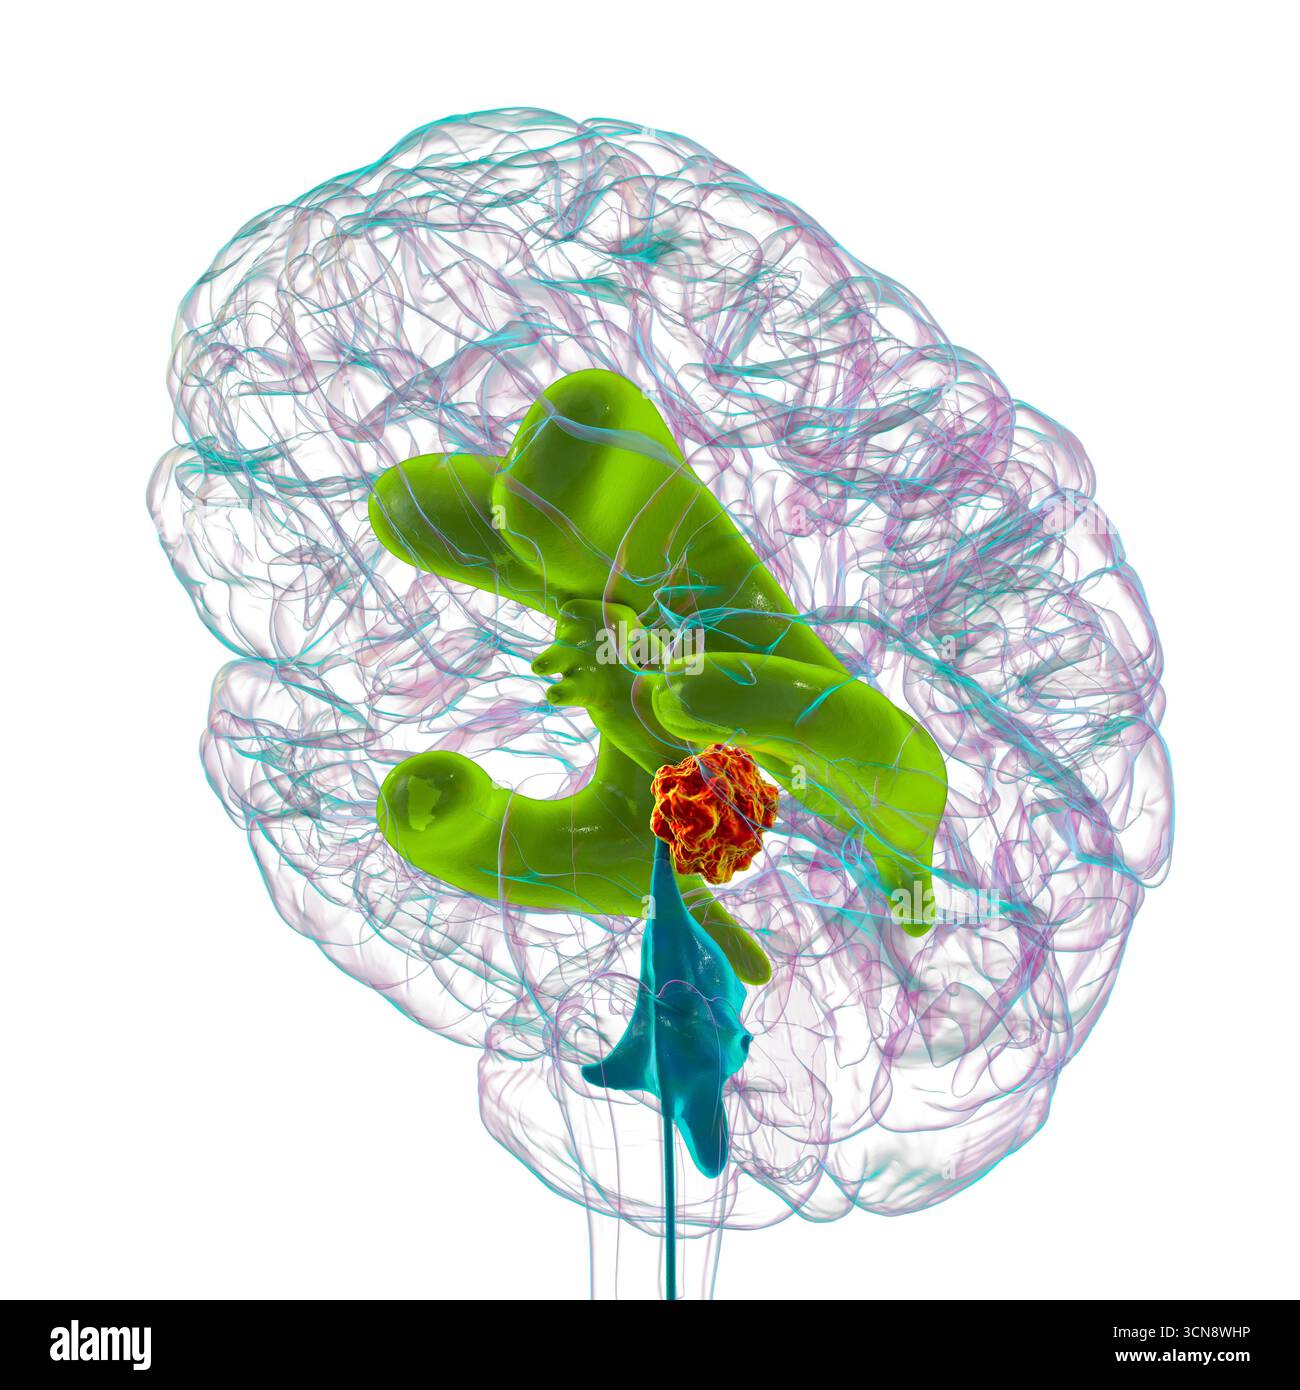

RF3CN8WHW–Darstellung der vergrößerten lateralen und dritten Ventrikel des Gehirns (Hydrozephalus), hervorgerufen durch einen Hirntumor, der den Aquädukt des Gehirns komprimiert.

RF3CN8WHP–Illustration des vergrößerten lateralen und dritten Ventrikels des Gehirns (Hydrozephalus), hervorgerufen durch einen Hirntumor, der den Aquädukt des Gehirns komprimiert.

RF3CPM9D2–Darstellung der vergrößerten lateralen und dritten Ventrikel des Gehirns (Hydrozephalus), hervorgerufen durch einen Hirntumor, der den Aquädukt des Gehirns komprimiert.

RF3CPM9D7–Darstellung der vergrößerten lateralen und dritten Ventrikel des Gehirns (Hydrozephalus), hervorgerufen durch einen Hirntumor, der den Aquädukt des Gehirns komprimiert.

RF3CPM9DA–Darstellung der vergrößerten lateralen und dritten Ventrikel des Gehirns (Hydrozephalus), hervorgerufen durch einen Hirntumor, der den Aquädukt des Gehirns komprimiert.

RF3CPM9D6–Darstellung der vergrößerten lateralen und dritten Ventrikel des Gehirns (Hydrozephalus), hervorgerufen durch einen Hirntumor, der den Aquädukt des Gehirns komprimiert.